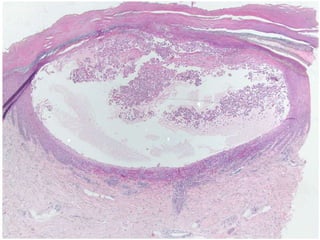

HISTOPATHOLOGIC FEATURES

Bullae are subepithelial, non-specific and similar to those of MMP.

 The inflammatory infiltrate is typically polymorphous, with

an eosinophilic predominance.

 Mast cells and basophils may be prominent early in the

disease course.

 Electron microscope shows basement membrane attached to

the connective tissue rather than overlying separated

epithelium.

 Tzanck smear shows only inflammatory cells.